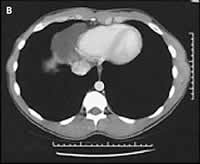

1名20岁的海军学校学生,在军队体格检查时被发现其胸部X线片异常,而来心脏科门诊。其自诉无症状,体格检查结果亦正常。X线胸片(图A)显示在右心膈角区有一平滑的密度边缘,它部分地遮盖了右心边界。CT扫描显示(图B),紧靠心脏的右边界有一均质的平滑病灶,其间没有分隔和钙化。大小约5.0 cm×4.4 cm×7.0 cm,而心脏和大血管均正常。超声心动图(图C)对该病灶进行了进一步评价,改良右胸骨旁角度证实存在一个充满液体的心包囊肿。由于该军校学生没有症状,并且心包囊肿是良性的,所以医师决定对其临床随访观察。